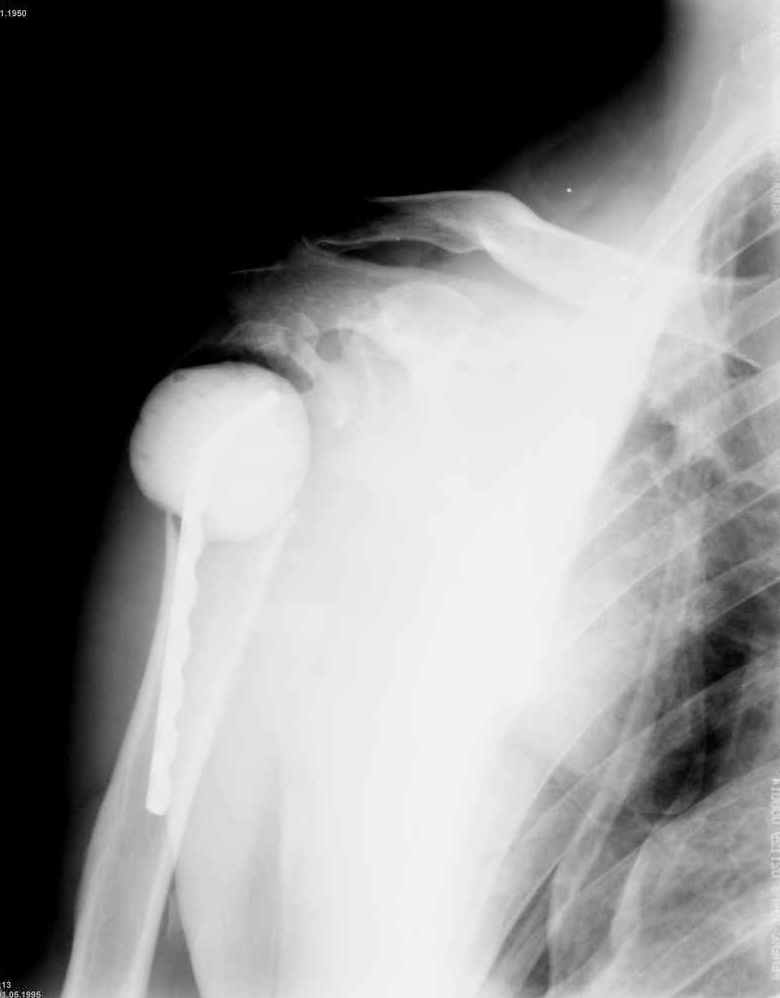

Уважаемые коллеги. Недавно из нашего отделения был выписан пациент 54 лет с закрытым переломом плечевой кости. Из анамнеза: за 2 дня до поступления в НИИСП, в состоянии алкогольного опьянения упал с лестницы на даче (высота 3-4 метра) с упором на правую руку. Через двое суток обратился за медицинской помощью. Доставлен бригадой "Скорой помощи".Правый плечевой сустав умеренно деформирован. По внутренней поверхности плеча имеется кровоподтек. При пальпации плечевого сустава имеется умеренная болезненность. Активные и пассивные движения болезненные. Снижена чувствительность по тыльной поверхности пальцев кисти и отсутствует активное разгибание кисти и пальцев. Имеется подкожная эмфизема шеи, верхней половины грудной клетки (рис 1, 2). На рентгенограмме: оскольчатый перелом головки плечевой кости со значительным смещением, перелом 2-3 ребер справа, тканевая эмфизема (рис 3). КТ при поступлении: перелом головки плечевой кости в области анатомической шейки со смещением отломка головки в грудную полость, правосторонний гидроторакс, перелом 2-3-4 ребер справа. (рис 4). Через двое суток после поступления выполнена операция: атипичная торакотомия, эвакуация свернувшегося гемоторакса, удаление инородного тела (головки плечевой кости) из плевральной полости (при этом выявлено имеющееся повреждение париетального и висцерального листков плевры) (рис. 5), дренирование плевральной полости, замещение проксимального конца плечевой кости спейсером из костного цемента с антибиотиком (рис. 6). Послеоперационный период протекал гладко. При контрольной рентгенографии положение спейсера удовлетворительное (рис. 7, 8). Дренаж из плевральной полости удален через 3 суток после вмешательства. Послеоперационная рана зажила первичным натяжением. Через 12 дней после операции больной выписан на амбулаторное лечение.

Я абсолютно согласен с Вами. Бугорки мы не выделяли и не фиксировали. Дело в том, что основная линия перелома проходит по анатомической шейке. И ниже нее кость повреждена, но существенного смещения осколков и бугорков до и во время операции не отмечено (прилагаю первичный снимок лучшего качества - рис. 1).